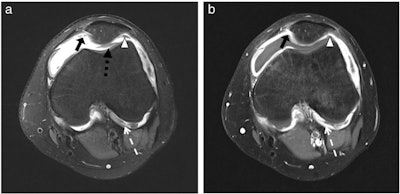

The MRI scans were retrospectively analyzed by three experienced radiologists in two readings, using the juvenile arthritis MRI scoring (JAMRIS) system and a modified international prophylaxis study group (IPSG) classification. In the first reading session, only unenhanced MR images were evaluated. In a second reading session, all images before and after contrast medium application were included. To avoid bias, an interval of at least two weeks was set between the two readings.

"This is the first study to show unenhanced MR images acquired on a [3-tesla] MRI to detect synovial thickening of the knee joint as reliably as on enhanced MR images," the authors concluded.